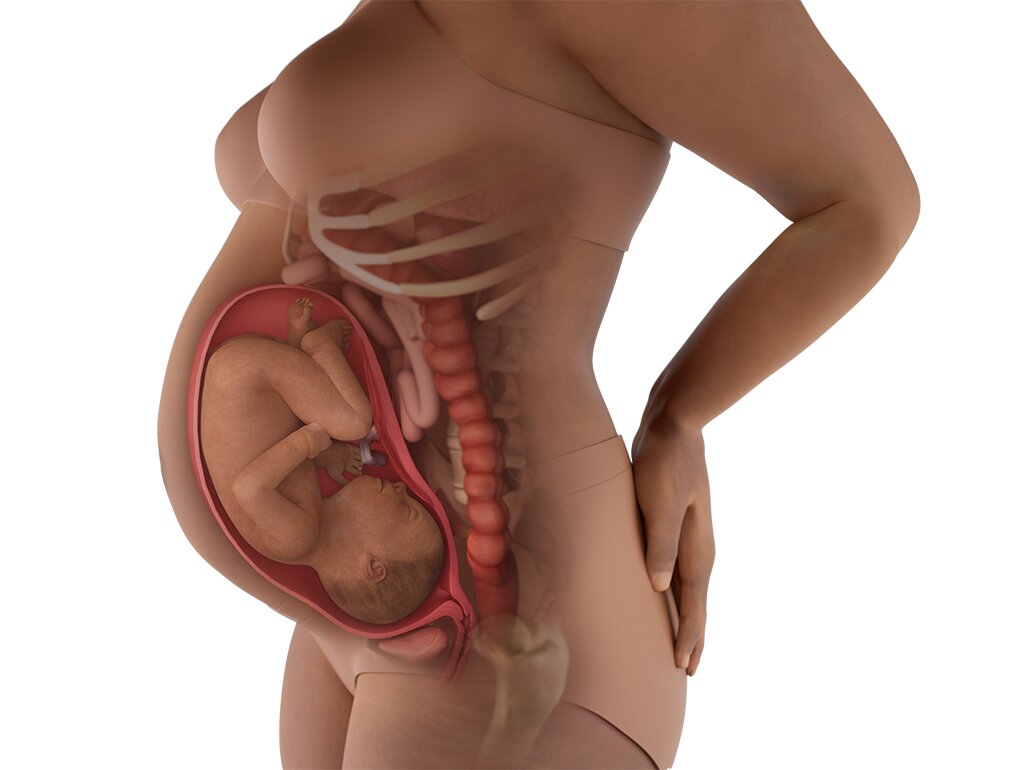

Perkembangan Janin 33 Minggu:

Pada minggu ke-33, tubuh janin semakin berisi karena lemak terus bertambah. Kulit tidak lagi terlalu keriput seperti sebelumnya. Tulang semakin kuat tetapi masih lentur. Janin biasanya sudah mulai jarang berputar karena ruang semakin sempit. Ibu mungkin sering merasakan perut kencang sesekali, dan ini bisa menjadi kontraksi latihan yang normal.

Kondisi Perut Bumil Hamil 33 Minggu